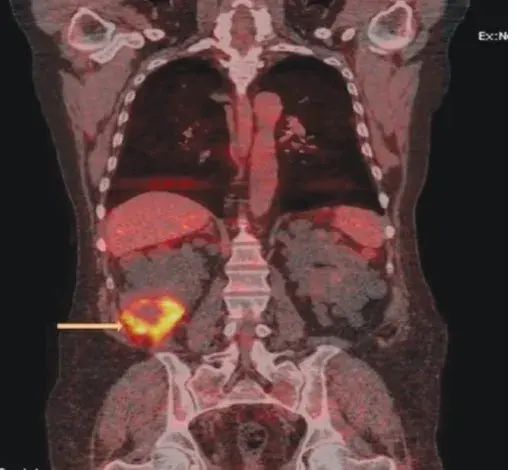

Caso muito ilustrativo publicado no Kidney 360 (link) Paciente do sexo feminino com 43 anos e com antecedente de nefrite lúpica (NL) proliferativa há 13 anos. A paciente apresentava histórico de acometimento grave da doença, com múltiplos tratamentos com infusões de metilprednisona e ciclofosfamida devido ao acometimento do sistema nervoso central (SNC) e da NL.